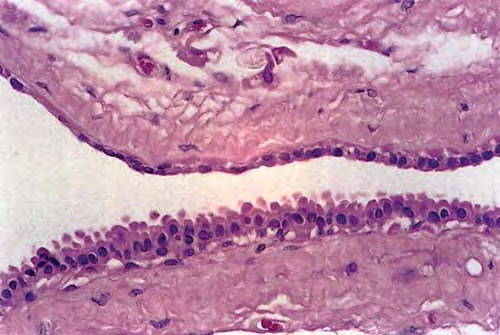

The clinical appearance of a pea-sized cyst near the inner canthus of the eye, which contains a thin clear or pigmented fluid, suggests an apocrine hidrocystoma; however, histologic examination often is required to establish a specific and definitive diagnosis. Upon histologic examination, apocrine hidrocystomas show large unilocular or multilocular cystic spaces within the dermis (see the image below). Apocrine hidrocystomas are more likely to be multilocular than the closely related eccrine hidrocystoma

The cyst wall is lined by apocrine-type secretory epithelium. The innermost layer of the wall is composed of a single (occasionally double) layer of cuboidal-to columnar-shaped cells. The nuclei of these cells are positioned basally. The outer layer of cells composing the cyst wall is formed by myoepithelial cells in which the long axes run parallel to the cyst wall.

Well-organized fibrous tissue surrounds the cyst. Papillary projections extend from the secretory layer into the cyst cavity, depicting decapitation secretion. The secretory cells contain periodic acid-Schiff–positive, diastase-resistant granules and occasionally contain pigment granules, which provide the brown color of the cystic fluid. This pigment is neither melanin nor hemosiderin. On electron microscopy, secretory cells have numerous, dense, lysosomal-type secretory granules typical of apocrine gland cells. They also have an increased number of annulate lamellae, which are unusual in normal apocrine cells.